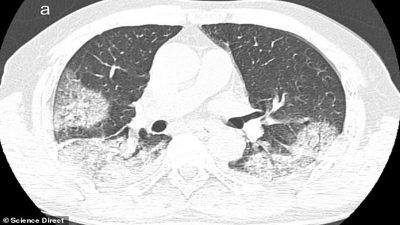

Los especialistas del Instituto Nacional de Enfermedades Infecciosas en Roma estudiaron los cuerpos de los pacientes de 65 y 67 años y detectaron, mediante rayos-X y tomografías computarizadas, un gran deterioro en la función de los pulmones.

Cuando coronavirus ataca los pulmones, provoca una inflamación en las membranas mucosas, lo genera un daño en los alvéolos pulmonares, que tienen que trabajar más para suministrar oxígeno a la sangre que circula por todo el cuerpo y eliminar el dióxido de carbono para que se pueda exhalar. La inflamación y el daño al flujo de oxígeno pueden causar que dichas áreas en los pulmones se llenen de fluido, pus y células muertas.